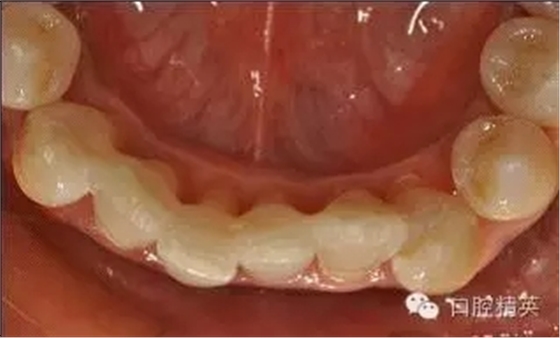

治療前: